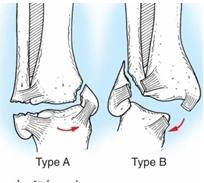

Рисунок 1 Типы переломов лодыжек

Переломы лодыжек возникают в основном при непрямой травме, причем важнейшее значение имеют боковые и ротационные движения. При подвертывании стопы кнаружи или кнутри происходят чрезмерные, выходящие за пределы физиологической возможности движения, которые приводят к разрыву связок голеностопного сустава или перелому костей. При подвертывании стопы, как правило, возникают и ротационные движения голени вокруг оси при фиксированной стопе.